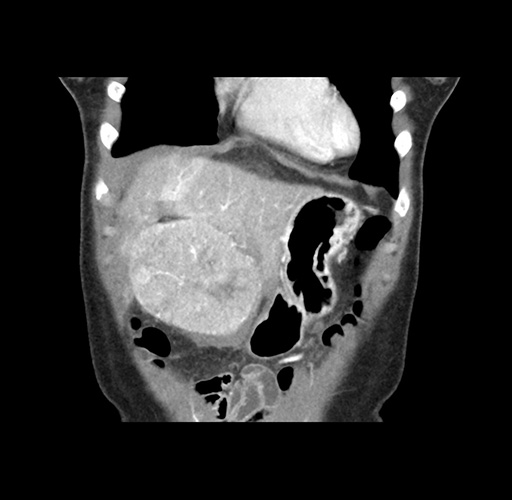

Imaging Analysis

Look through the patient's CT scan to identify any areas of concern for the necessary procedure.

Based on your CT findings, which issue(s) would give reason for "planned slowing down moment(s)" in this case?

Considering a standard left lateral sectionectomy procedure, what step(s) of the operation would you do differently in this case ?